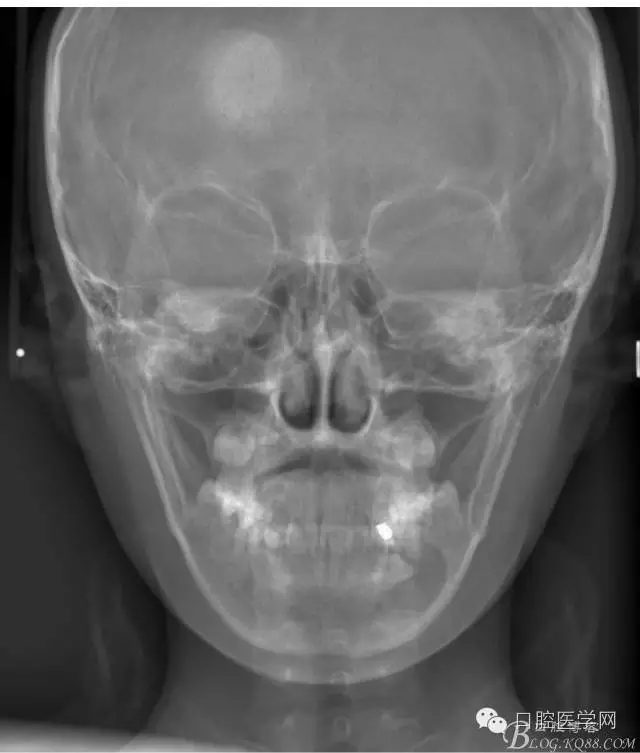

正畸查:替牙合。第一恒磨牙中性合。上牙弓尖圓型下牙弓方圓型。前牙覆合3度覆蓋7.5mm。下前牙咬到上舌側(cè)牙齦。上頜擁擠4.0mm,下頜擁擠

3.0mm。上頜稍前突下頜后縮,上下唇前突,上前牙覆蓋下唇,下唇外翻。面下三分之一過短,頦唇溝明顯,開唇露齒,頦饜窩明顯。顳下頜關(guān)節(jié)開閉口無彈響,無壓痛,開口型開口度正常。